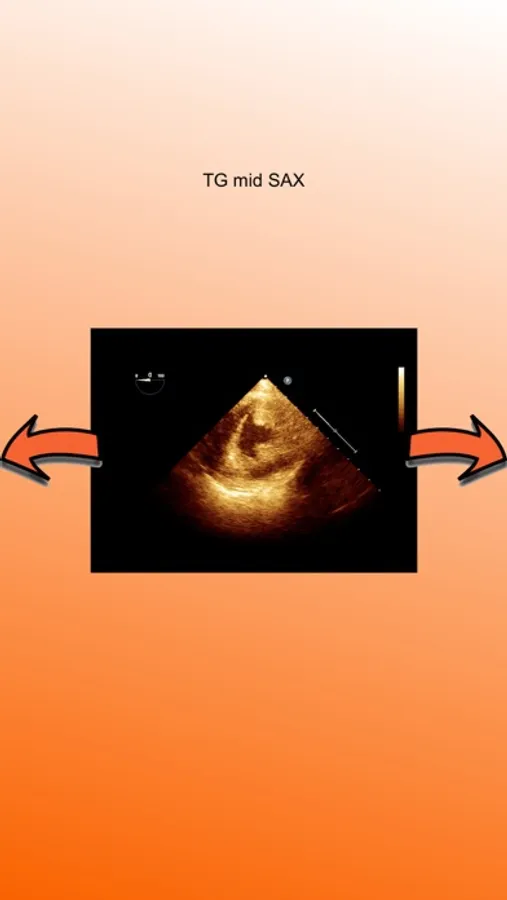

Standard Transesophageal echocardiographic views are represented and videos are easily visualized.

Legend for all views are included.

The application is dedicated to physicians, nurses or technicians who approaches to Transesophageal Echocardiography.